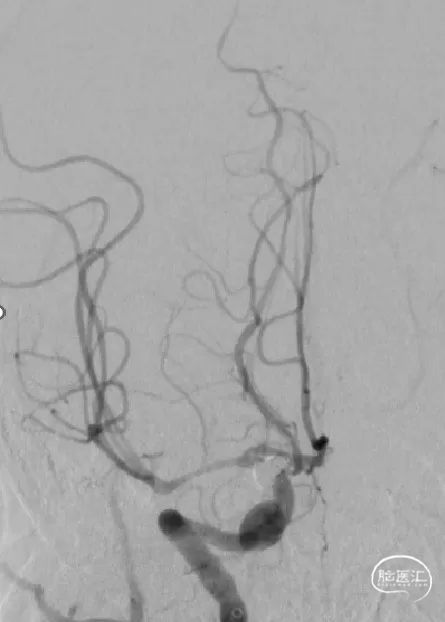

工作角度造影

右侧颈内动脉正位造影

右侧颈内动脉侧位造影

沿微导管填入第一个圈通桥凤弹簧圈AEC-05-15-S,成篮。

继续填塞填塞第二个圈通桥凤弹簧圈AEC-04-10-S,成功解脱。

继续填塞填塞第三个圈通桥凤弹簧圈AEC-03-08-S,成功解脱。

继续填塞填塞第四个圈通桥凤弹簧圈AEC-02-04-S,成功解脱。

继续填塞填塞第五个圈通桥凤弹簧圈AEC-02-04-S,成功解脱。

继续填塞填塞第六个圈通桥凤弹簧圈AEC-01-03-S,收尾,成功解脱。

在填塞过程中,通桥凤弹簧圈能很好的顺应瘤体形态,钻孔能力较强,圈体相对柔软,在填塞过程中几乎不踢管。机械解脱释放比较稳定,一折一拉,即刻解脱。

合理的弹簧圈选择是手术成功的先决条件。通桥凤弹簧圈超柔软的特性,顺应性更好,更容易进入更小的空间,对瘤壁压力更小,顺应瘤体形态,对于不规则动脉瘤、小动脉瘤和破裂动脉瘤安全致密填塞优势显著。